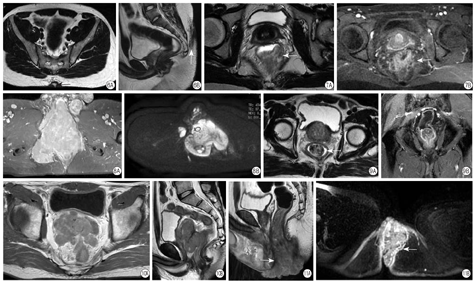

肛瘘患者检查前无需清洁肠道,可于排空小便半小时后(使膀胱适度充盈)开始扫描。常规的扫描序列包括轴面T1WI、T2WI及T2WI压脂序列,DWI,LAVA动态增强序列,矢状面T2WI及LAVA增强,冠状面T2WI及LAVA增强序列。典型的瘘管在MRI上表现为条状长T1(等)长T2信号,压脂像和DWI上表现为高或稍高信号,增强扫描见明显强化;肛周脓肿则表现为明显环形强化,其内部脓液无强化(图2)。对于术后纤维瘢痕,平扫及增强序列均为低信号。

在肛瘘的诊断报告中,需要描述其分型、内口的位置及个数、内口距离肛缘的距离、是否合并脓肿以及是否存在周围组织炎性反应等等。需要注意的是,通过对比轴面、矢状面和冠状面图像,要对瘘管的走行进行详细的描述,然后做出正确的分型诊断。有文献指出,外科医师在忽略MRI诊断的情况下进行肛瘘手术的话,术后复发率高达52%;而结合MRI后进行手术的话则可降低75%的复发率[10]。因此对于肛瘘及肛周脓肿的患者来说,MRI在术前指导及术后复查方面都具有非常重要的价值。

目前痔的诊断主要依靠临床检查,如肛门视诊、指诊、肛直肠镜检查等,结合患者临床表现多可作出明确诊断,影像学检查可明确病变的部位及范围,有效地指导临床施行合理的手术方式,避免诸多危急并发症的出现,并可起到辅助诊断及鉴别诊断的作用,主要的检查方法为MRI,其中内痔可表现为肛管中上段局部黏膜肿胀,增强扫描呈渐进性强化,强化程度高于周围正常肛管壁;较典型的外痔表现为肛门口处梭形或结节状肿物脱出,强化程度与内痔相似(图3);混合痔则兼有此二种表现。

MRI对肛裂的诊断具有一定的价值,但是多需结合临床病史才能明确诊断,MRI多表现为黏膜下条状长T1、短T2信号,增强扫描可见裂隙状强化,伴感染时可见周边片状强化(图4)。已确诊肛裂时,一般不宜进行肛门指检及肛门镜检查,以免引起剧痛。需要注意的是,克罗恩病合并肛裂时,患者临床症状多不明显,最终的确诊需要结合临床检查和影像学检查。

影像学检查特别是MRI对其诊断的价值非常大,骶尾部X线可初步判断周围骨质有无破坏,超声检查可发现骶前囊性肿块,但对于了解囊性肿物与周围脏器的关系,尚有一些欠缺,因此可作为初步检查。MRI对囊肿的准确定位、大小以及与周围重要脏器、血管的关系,有非常重要的价值,高场磁共振成像(MRI)的软组织分辨率更高,能多方位显示骶前囊肿本身特点及其周围的解剖结构(图5),可以有效地指导临床下一步治疗方案的确定。

MRI能够对病灶进行准确地定位,并且通过增强扫描可以初步判断病灶中脓液的量,诊断的准确性较高,有文献报道其敏感性为86%,特异性为100%[14],因此具有很高的应用价值(图6)。根据MR上环形强化的脓肿及瘘管走形特征,多能作出诊断,出现误诊的主要原因是对藏毛窦疾病的认识不足。

典型的病灶在MRI图像上表现呈长T1、稍长T2信号,增强扫描可见明显强化或不均匀强化,结合相关病史多可做出诊断。肛管癌要综合MRI、病理及生化检查结果共同做出最终诊断,MRI的主要作用是对肿瘤进行准确的分期,以指导临床下一步的治疗措施的制定及后续的治疗后复查。

在MRI诊断的过程中,肛管癌需要与肛周脓肿及肛管黏膜炎性反应相鉴别,肛周脓肿呈典型的环周强化,而炎性反应则边界较模糊,没有肿瘤的占位效应(图7)。

MRI对于肿瘤的定位及浸润范围的确定有较大的价值,可明确肛门括约肌、肛提肌以及周围组织器官是否受累。肿瘤在T1WI上为稍低信号,由于内部可出现出血坏死等改变,T2WI上表现为混杂稍长T2信号,DWI为高信号,增强扫描肿块呈明显不均匀强化(图8)。

MRI上主要表现为T2WI及压脂像上黏膜层边界模糊的高信号,增强扫描可见肛管黏膜血管扩张充血(图9)。

MRI表现为肛周长T1(等)长T2信号,边缘多较光整,增强扫描可见轻中度强化(图10),也可呈浸润性生长,表现为与周围组织器官分界欠清晰。

尖锐湿疣主要通过临床病史及相关临床检查来诊断,影像学检查的作用主要是明确病变范围以及与周围肌肉及组织器官的关系,较小的病变MRI诊断困难,当病灶较大时,MRI可表现为肛周肿物,多呈菜花样或多个融合结节影,平扫呈长T1、混杂稍长T2信号,增强扫描可见不均匀强化(图11)。本病需要与肛管癌及其他肛周恶性肿瘤相鉴别,结合临床病史及相关标志物的筛查,多可作出明确诊断。